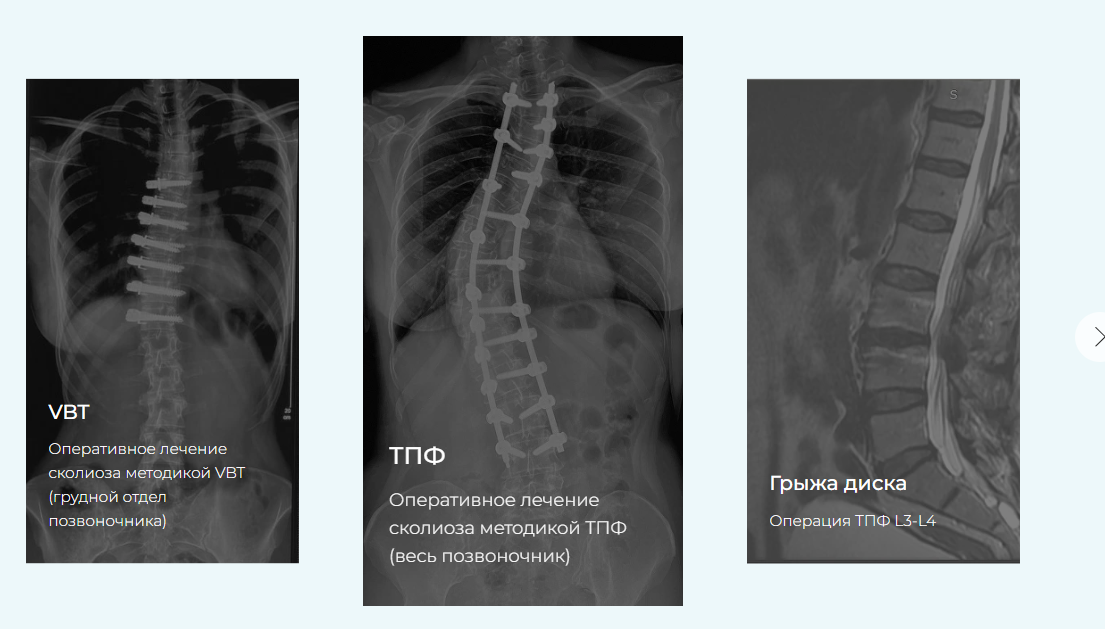

Реабилитация после операций на позвоночнике. Тариф Базовый (Семён Семендуев)

Этот курс разработан для восстановления пациентов спустя 3 месяца после операций по исправлению сколиотической деформации (методиками ASC, VBT и ТПФ), по исправлению кифотической деформации, удаления грыж межпозвонкового диска с фиксацией и без, фиксации после переломов позвоночника грудного и поясничного отделов, устранения спондилолистеза, а также для консервативного лечения остеохондроза и болей в спине.